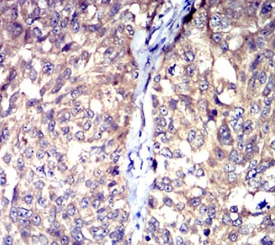

HTR3A Mouse Monoclonal antibody[3B11]

The product of this gene belongs to the ligand-gated ion channel receptor superfamily. This gene encodes subunit A of the type 3 receptor for 5-hydroxytryptamine (serotonin), a biogenic hormone that functions as a neurotransmitter, a hormone, and a mitogen. This receptor causes fast, depolarizing responses in neurons after activation. It appears that the heteromeric combination of A and B subunits is necessary to provide the full functional features of this receptor, since either subunit alone results in receptors with very low conductance and response amplitude. Alternatively spliced transcript variants encoding different isoforms have been identified.

Immunogen:    Purified recombinant fragment of human HTR3A (AA: extra 24-157) expressed in E. Coli.

IHC    1/200 - 1/1000